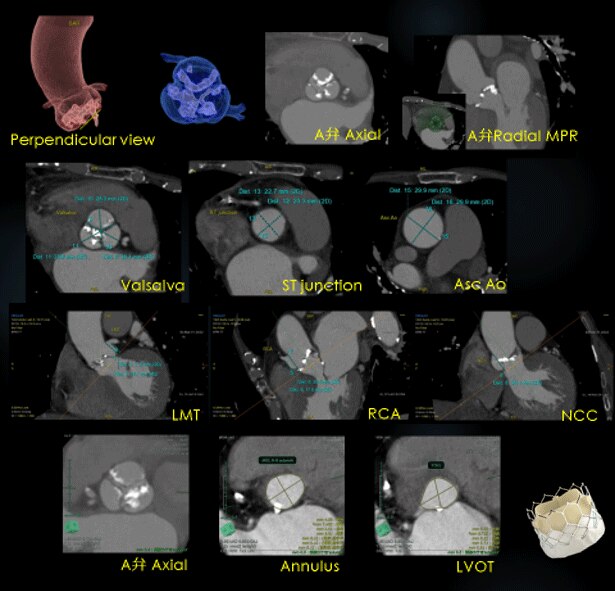

重度の大動脈弁狭窄症に対して行われるTAVIの術前検査では、ガイドラインにも示されているようにCTでの評価が一般的となっています。

大動脈弁複合体の評価として、まず拡張期にて大動脈弁の形態、石灰化の量や分布が評価できる画像をVR、MPRで提供しています。また弁輪破裂のリスクが高い石灰化の有無の評価、冠動脈分岐部の高さ(冠動脈閉塞のリスク予測)の計測など、大動脈基部と大動脈弁の評価などを行っています。

TAVIにおける弁輪径の計測およびリスク

TAVI弁には、大きく分けて2種類の弁があり、sapienシリーズは面積から算出した弁輪径を用い、Evolut Rは外周長を用いてサイズを決定しており、弁輪径の計測は弁のサイズ選択に影響を与えます。